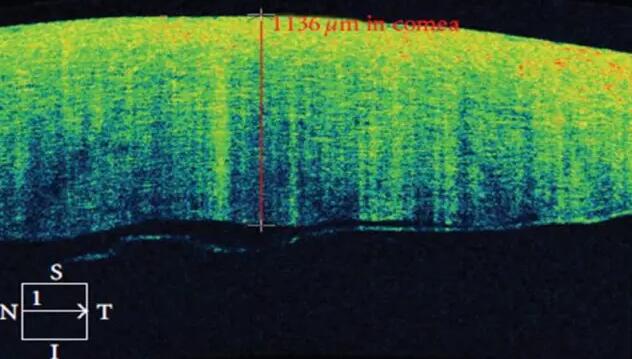

2、角膜厚度评估,角膜水肿、瘢痕、混浊、溃疡、异物、炎症、胬肉等断层观察

3、角膜屈光手术后角膜瓣观察、角膜厚度评估等